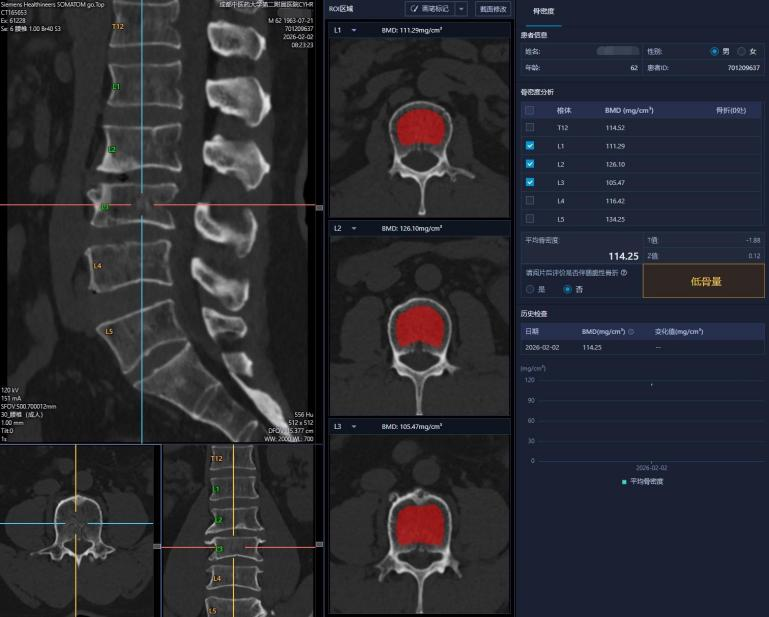

3. 智能分析:扫描后,医生在专用软件上选取椎体中心的松质骨区域,系统自动对照体模计算出精确的骨密度值,并生成三维图像和报告。